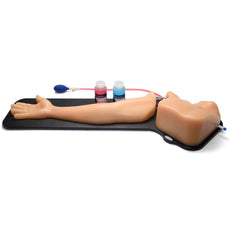

Sonohysterographay & Sonosalpingography Transvaginal Ultrasound Training Model

Sonohysterographay & Sonosalpingography Transvaginal Ultrasound Training Model

Gain proficiency in performing transvaginal ultrasound exams with our CAE Blue Phantom female pelvis models. The patented Simulex internal tissue allows learners to develop, practice and verify ultrasound imaging skills, including using ultrasound system controls, positioning and moving the transducer, recognizing internal pelvic anatomy and pathology and using gynecological ultrasound calculation packages to measure cysts, masses, and other structures. These models are excellent for 2D, 3D, and 4D ultrasonography imaging techniques. Choose from three options: General Pathology, Intrauterine & Ectopic Pregnancy, or Sonohysterographay & Sonosalpingography.

Sonohysterography & Sonosalpingography ANATOMY:

- Endovaginal canal

- Cervix

- Cervical canal

- Uterus

- Endometrial canal

- Fibroids

- Bladder

- Patent fallopian tubes

- Bowel

Dimensions:

- Size: 18 x 18 x 12 in.

- Weight: 22 lbs.